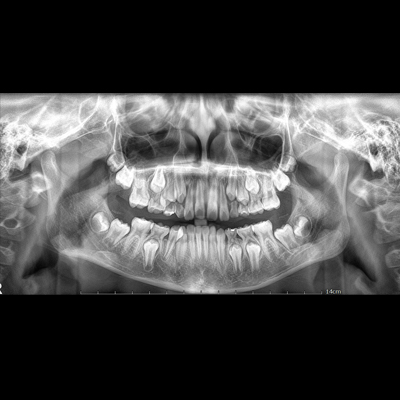

Rəqəmsal Panoramik və Sefalometric rentgen sistemi

-Yüksək keyfiyyətli görüntü sistemi, Çoxsayılı seçim funksiyası

-Yarı Tomoqrafik görüntüləmə (istəyə görə dəyişilə bilən)

-Çeşidli Panoramik Proqram

-Qatlanan Struktur